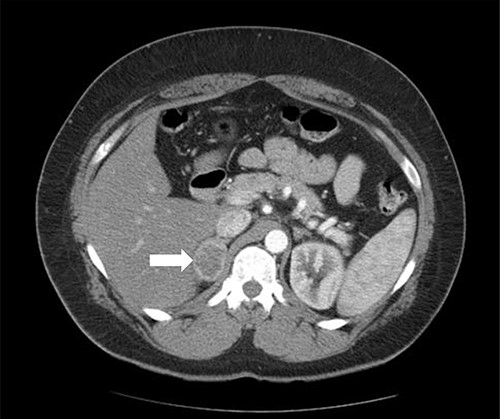

Patient 1 is a 45-year-old male, who came to our private clinic complaining of obesity with a body mass index (BMI) of 41 kg/m2. His other comorbidities included hypertension (HTN) controlled on one anti-HTN medication and diabetes mellitus (DM) on oral hypoglycemic agents (OHA). He denied any symptoms of reflux or any family history of adrenal/thyroid/parathyroid diseases. He was discovered to have a 4 cm right adrenal incidentaloma on a contrast-enhanced computed tomography (CECT) of the abdomen as a workup for abdominal pain (Fig. 1). Preoperative preparation included obesity workup with complete blood count, coagulation profile and a chest X-ray. Endocrine workup included a screening for possible functional incidentaloma, with adrenocorticotropic hormone of 2.8 pmol/l, aldosterone/renin ratio (ARR) of 1.7 ng/dl per ng/(ml·h), serum metanephrine of 343 pg/ml (reference <90), serum normetanephrine of 401 pg/ml (reference <129) and a normal serum morning cortisol of 168 nmol/l (reference 101–535). A diagnosis of right adrenal pheochromocytoma was established. A cardiac consultation was done and determined that the patient is fit for surgery and formulated a preoperative medication with α- and β-blockers.

Axial CT of the abdomen showing the right adrenal mass in Patient 1 (white arrow).